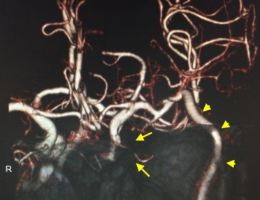

大型脳動脈瘤など、治療が困難とされる動脈瘤においても、バイパス術など高難度な手技を併用する手術や、フローダイバーターを用いた最先端の血管内治療を駆使して、安全に、かつ根治できるように努めています。

物が二重に見えるようになって発症した内頚動脈大型動脈瘤(矢印)の症例です。クリッピング術で直接動脈瘤をつぶすことができないため、バイパス術(矢印)を増設し内頚動脈を遮断することで動脈瘤を治療しました。